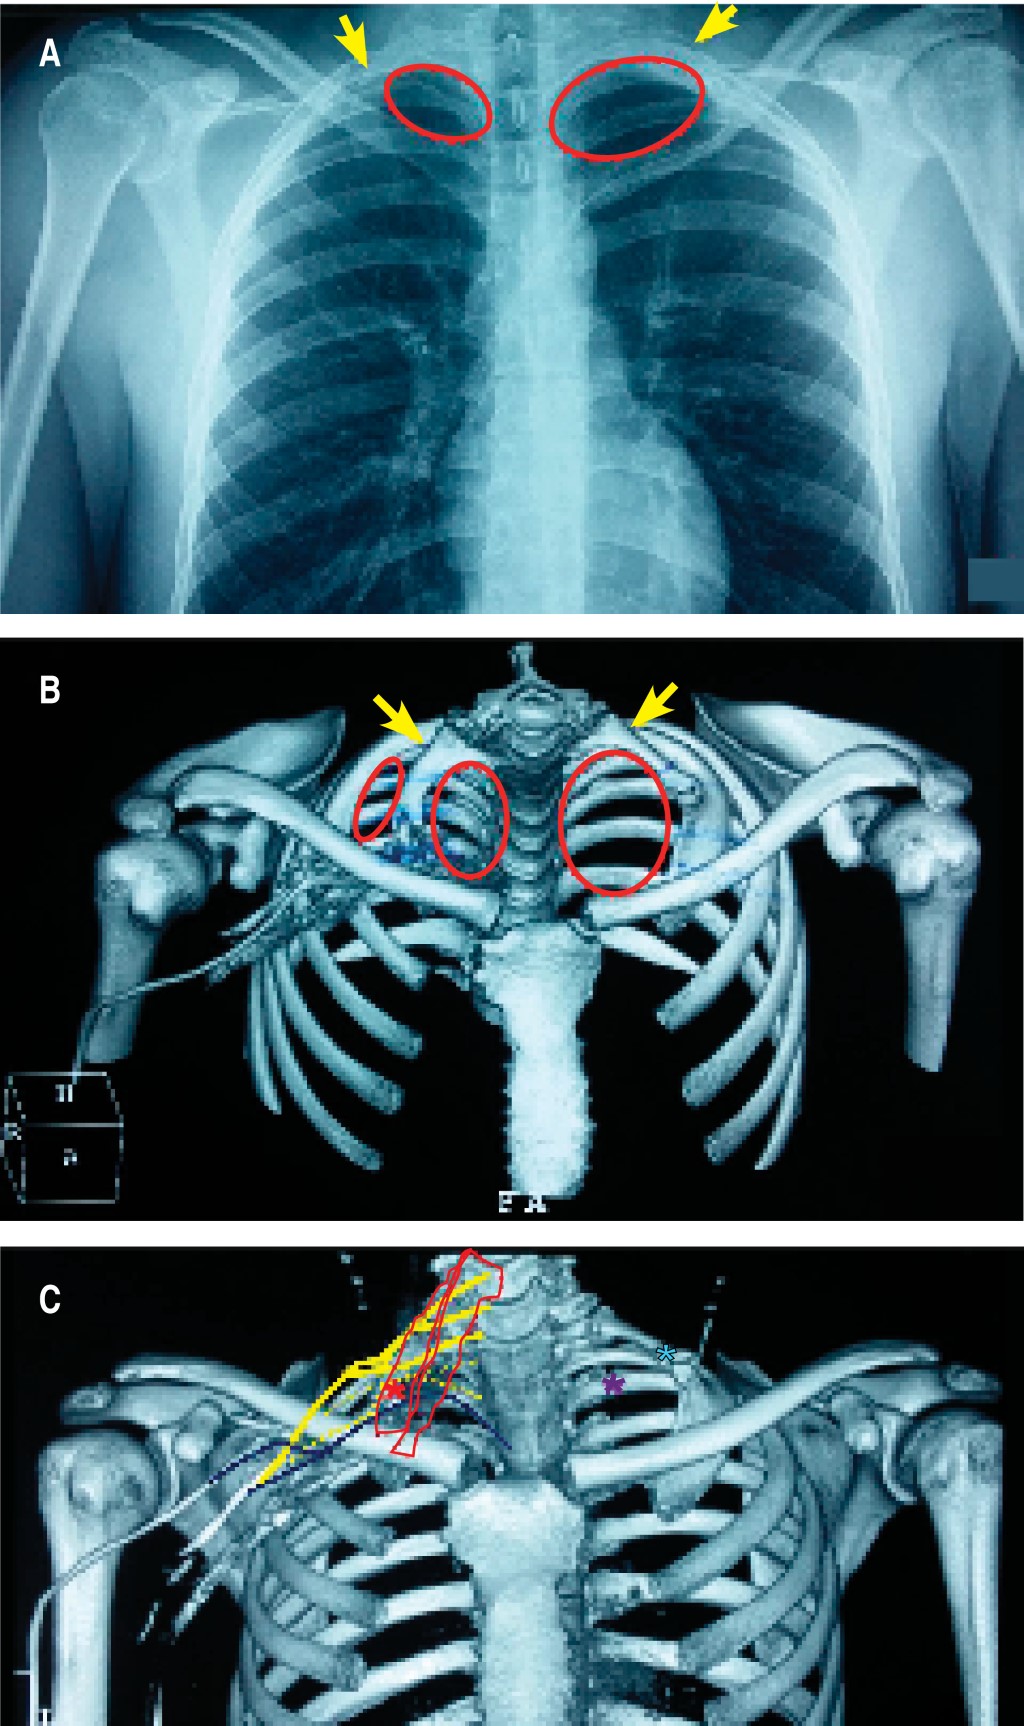

El estudio de electroconducción reveló disminución del reclutamiento de las fibras: 1o interóseo dorsal derecho, extensor del índice derecho, con normalidad de los grupos proximales del miembro superior al igual que el de los flexores y extensores comunes de los dedos, hallazgos de afección tronco inferior del PB derecho, el lado izquierdo no tuvo síntomas ni signos en el examen físico, la electroconducción indicó normalidad en el lado izquierdo. En imagen, la radiografía de tórax y tomografía demostraron costillas cervicales: derecha con el extremo distal libre y la izquierda con su extremo distal articulada en la cara posterior del tubérculo del músculo escaleno anterior de la primera costilla. En el estudio vascular de reconstrucción venosa se observó diminución calibre de la vena axilar derecha en el lugar del CONV (Figuras 1A, B, C y 2A).

Se realizó intervención quirúrgica, exéresis de CC y abordaje supraclavicular, se evidenció CC derecha articulada a la apófisis transversa C6, con borde libre estrechando el opérculo torácico (OCT), el tronco nervioso inferior del PB derecho se encontró comprimido y deformado, se realizó neurólisis, adherenciólisis del lugar del conflicto con trasposición, liberación del segmento comprimido y fresado del borde superior de la primera costilla (Figura 2B).

En el caso que presentamos, el paciente consulta por cuadro de cervicobraquialgia derecha con evidencia de neuropatía del tronco inferior del PB, la imagen demostró el lado derecho la costilla accesoria con borde libre, lugar del CONV (tipo II), mientras que el lado izquierdo sin sintomatología, la costilla accesoria tiene articulación verdadera con la primera costilla (Tipo I), el examen físico demostró con las pruebas de provocación compromiso vascular, por lo que revela un dato importante de SOCT arterial y neural.